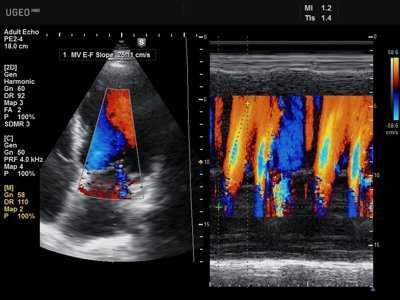

2.7.4. Стресс-эхокардиография

Один из самых востребованных и высокоинформативных методов неинвазивной диагностики ИБС. В основе метода лежит визуальное выявление локальной дисфункции левого желудочка во время физической нагрузки или фармакологической пробы. Стресс-ЭхоКГ превосходит обычную нагрузочную ЭКГ по диагностической ценности, обладает большей чувствительностью (80— 85%) и специфичностью (84—86%) в диагностике ИБС. Метод позволяет не только доказательно верифицировать ишемию, но и предварительно определить симптом-связанную коронарную артерию по локализации преходящей дисфункции левого желудочка. При технической возможности метод показан всем больным с доказанной ИБС для верификации симптом-связанной коронарной артерии, а также при сомнительных результатах обычной нагрузочной пробы в ходе первоначальной диагностики.

5. Стресс-эхокардиография (с использованием физической нагрузки, чреспищеводной электростимуляции или медикаментозной нагрузки). Широко применяется у больных с ишемической болезнью сердца.

Главной предпосылкой, которая лежит в основе метода стресс-эхокардиографии, является тот факт, что возникновение ишемии миокарда сопровождается нарушением сократимости левого желудочка. Вследствие длительного или полного прекращения коронарного кровотока развивается острый инфаркт миокарда. Если нарушение кровоснабжения миокарда носит преходящий характер, то появляющееся патологическое движение стенки левого желудочка служит маркером, позволяющим определить место расположения и выраженность нарушения кровоснабжения сердечной мышцы.

Сократимость левого желудочка нарушается после снижения кровотока, но до появления характерных изменений на электрокардиограмме и приступа стенокардии. Этот ишемический каскад известен давно. Кардиологи используют протокол оценки функциональной способности сердца в ответ на физическую нагрузку с одновременным мониторированием электрокардиограммы и гемодинамических параметров.